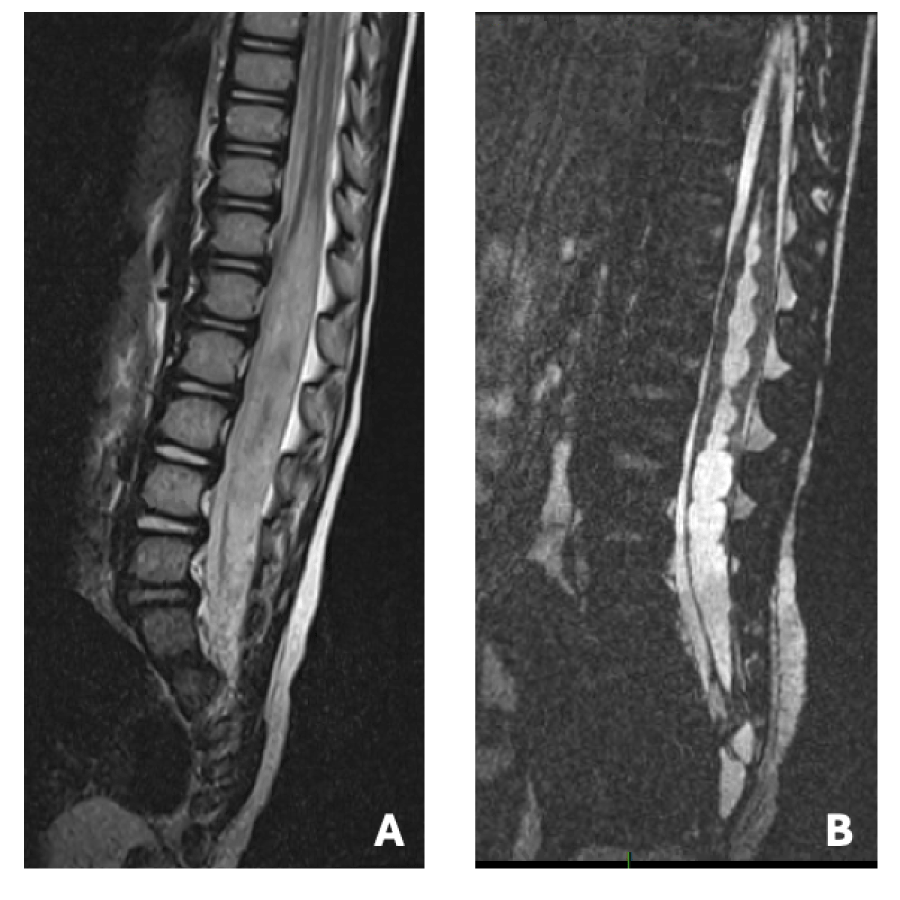

MRI 4 months post-surgery showed regression of the large syringomyelic cavity and signal abnormalities (figure 2). Bladder and renal ultrasound ordered at the same time was also normal. She was potty trained by 2 years and 3 months old. The last clinical follow-up was made earlier this year, she is now almost 4 years old and remains completely asymptomatic.

Figure 3: MRI findings at 4-month post op follow up with complete clinical recovery A: sagittal T2showing complete regression of syringomyelia and restoration of perimedullary intradural CSF space, B: Axial T1 showing the lipomatous remainder at termination of spinal cord View Figure 3